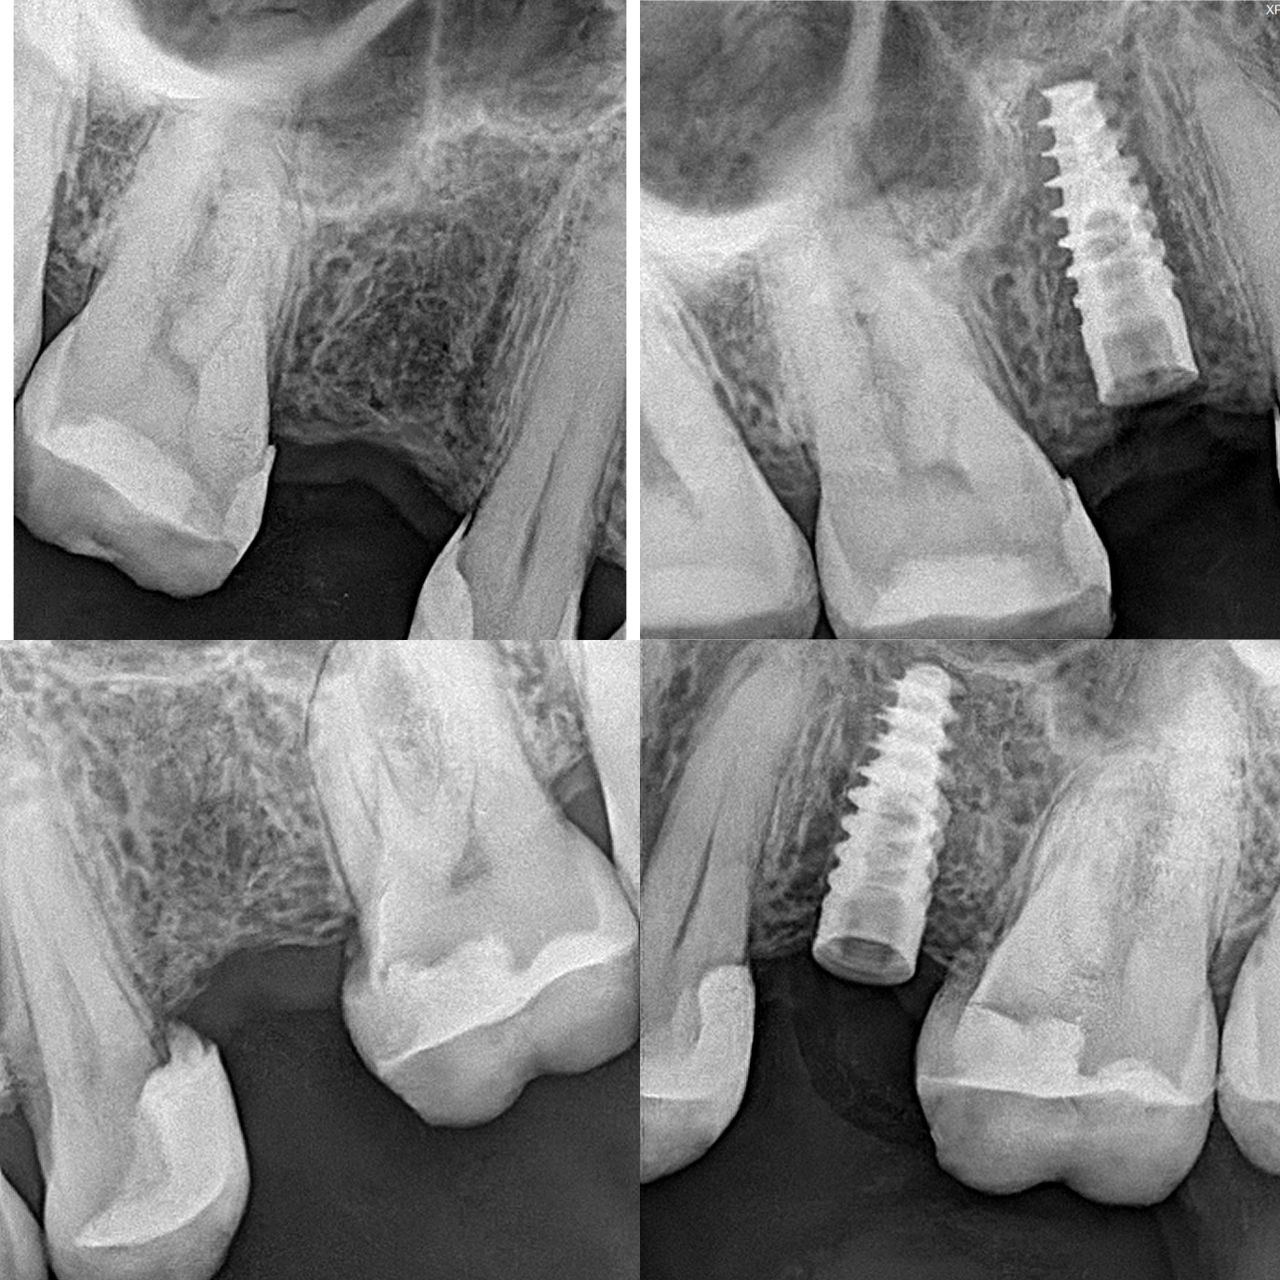

- Implantología dental

- Pérdida de dientes